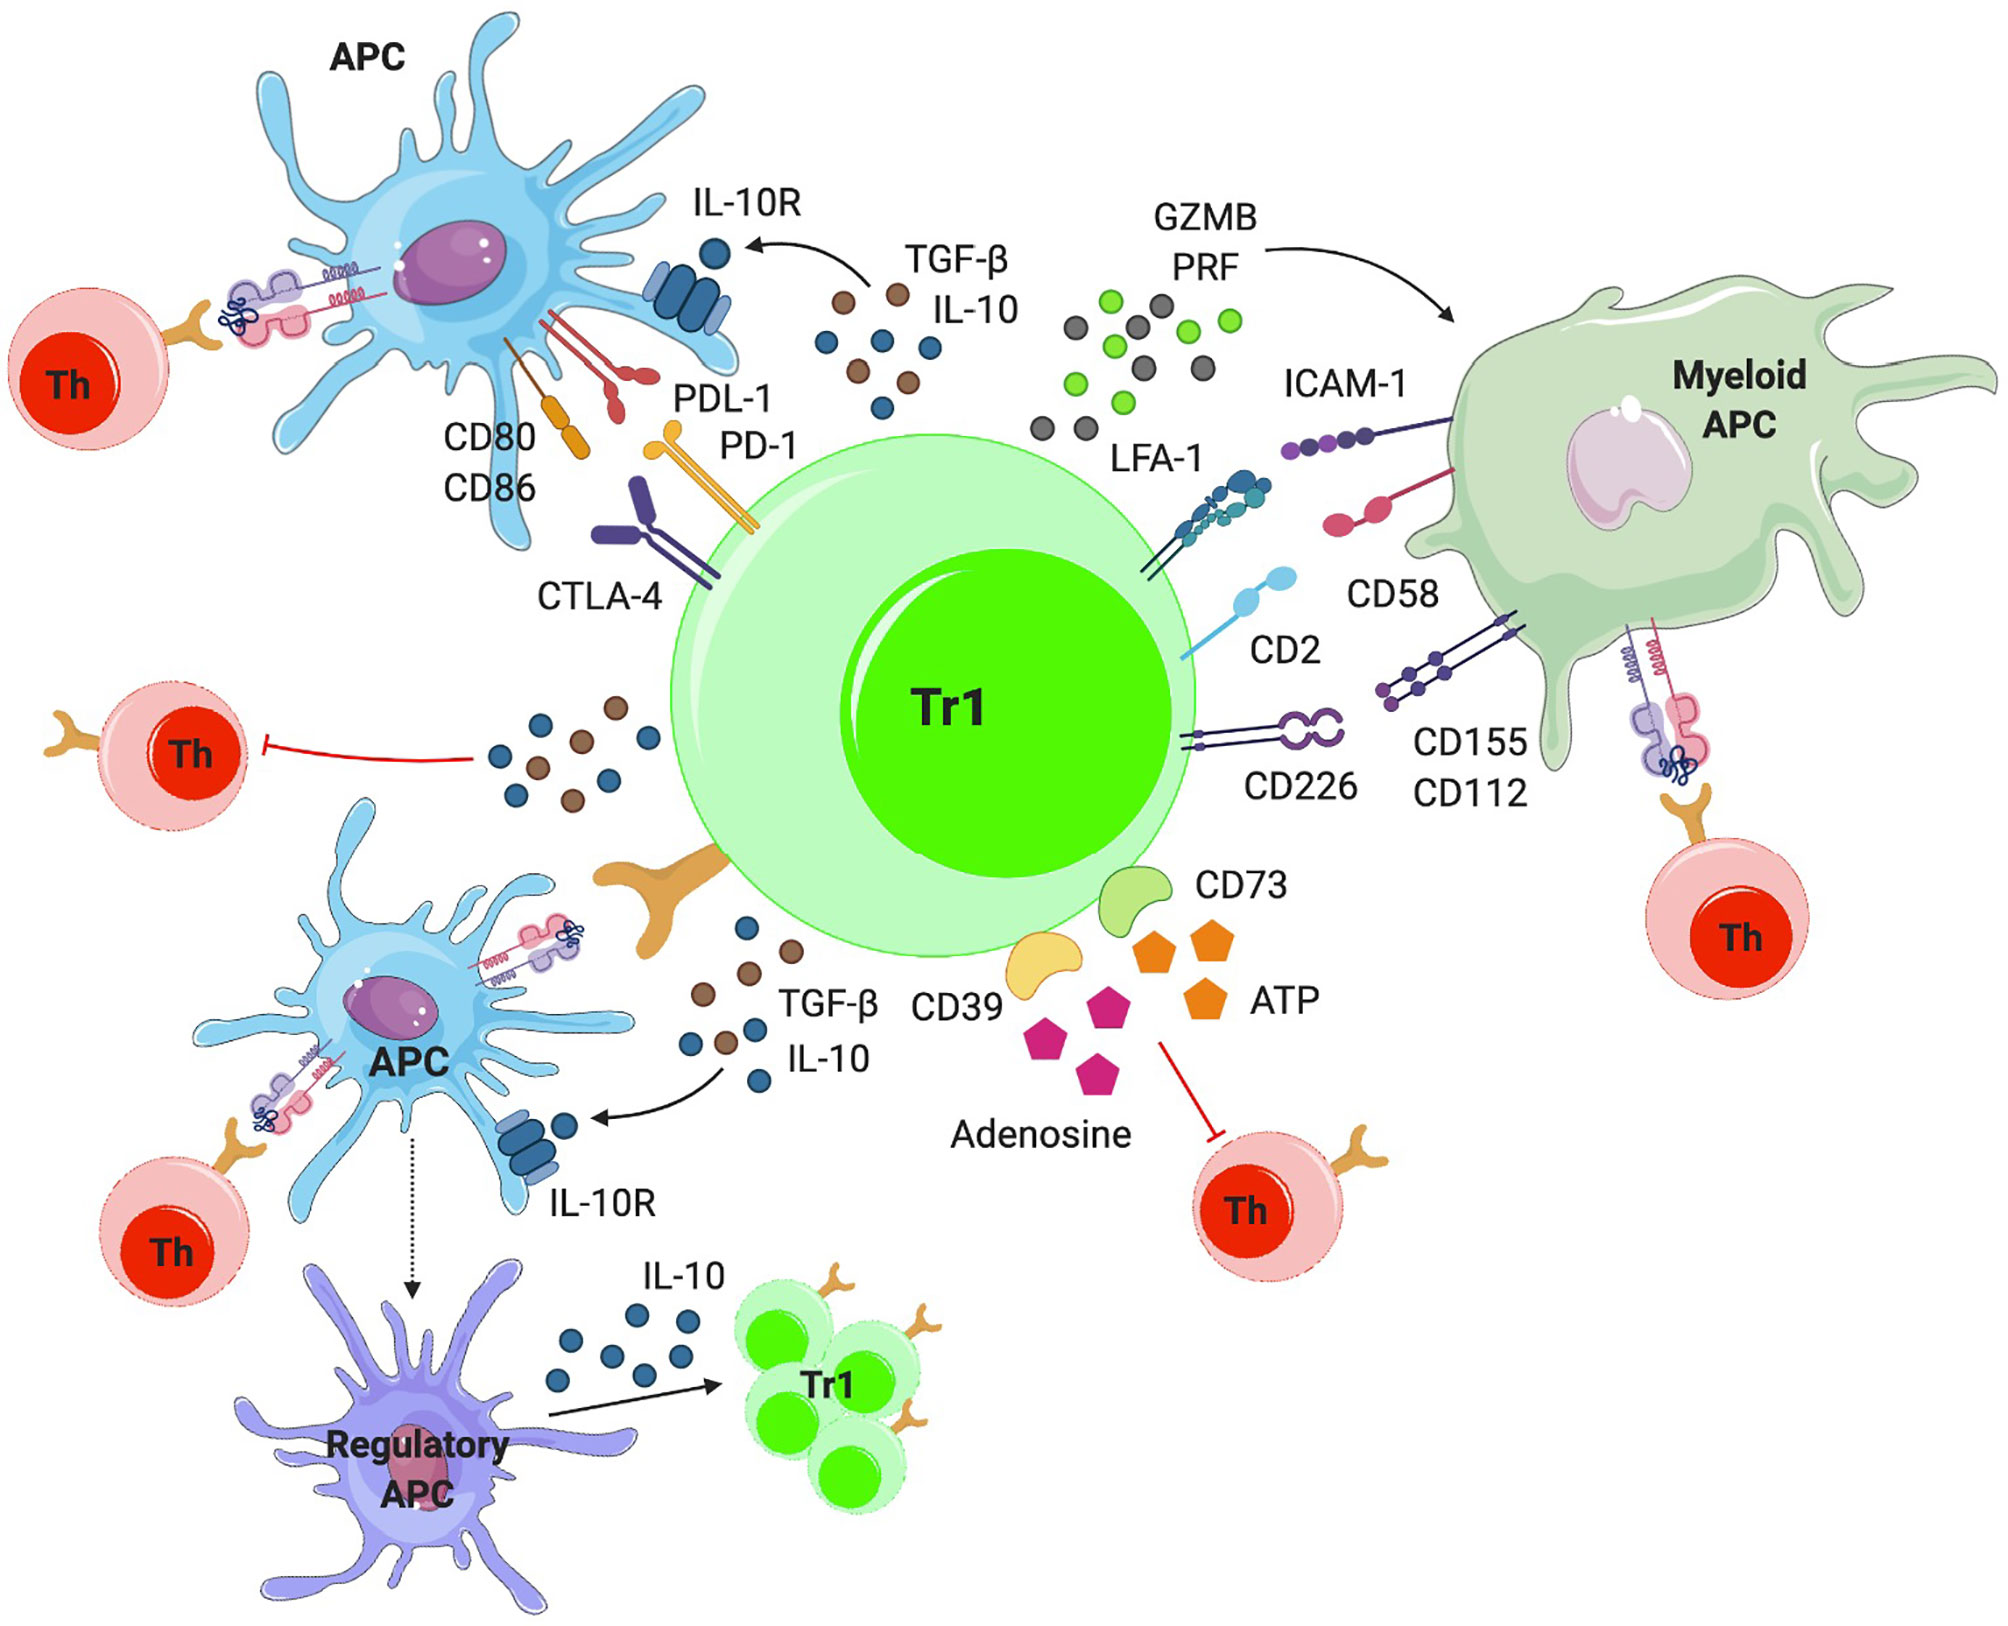

Иллюстрации из Cell Discovery: Удивительный мир науки через фотографии

Раздел: Фотоэссе